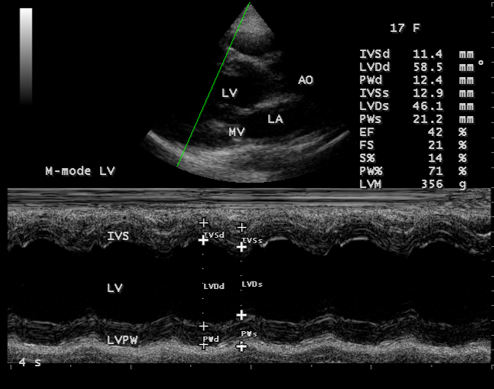

Figure 13: M-mode LV study (green line) showing moderate LV dysfunction with an ejection fraction of 42% in a 17-year old female in acute severe aortic regurgitation.

Since the patient had a bicuspid aortic valve as shown in Figure 9 and a history of rheumatic fever during childhood, rheumatic inflammation occurred on the aortic valve and harboured the infective vegetation through the vascular access during the treatment of febrile episodes. Patients with infective endocarditis are at risk of developing acute aortic regurgitation and the ECG can appear normal as in Figure 1 and the chest X-ray usually shows pulmonary edema with normal heart size. A dilated left ventricular cavity with a normal left atrium as in Figure 12 indicates that the volume overload on the left ventricle resulted a compensatory mechanism to maintain an adequate forward stroke volume by accomodating a large regurgitant fraction without an increase in end-diastolic pressure. The heart rate appeared normal (87 bpm) as the result of this compensation. Even though the aortic regurgitation is acute as in Figure 10 which showed a steep deceleration slope with a narrow width of regurgitant jet due to endocarditic lesion of aortic valve (endocarditic regurgitation). It is compensated in this patient and showed a lesser degree of decompensation as moderate LV dysfunction with an ejection fraction of 42% as in Figure 13, necessitating elective aortic valve replacement along with removal of vegetations with a mechanical prosthetic valve. Anticoagulation with warfarin to maintain the INR (international normailised ratio) between 2 to 3 is indicated after the clearance of active stage of endocarditis with antibiotic therapy and surgery.